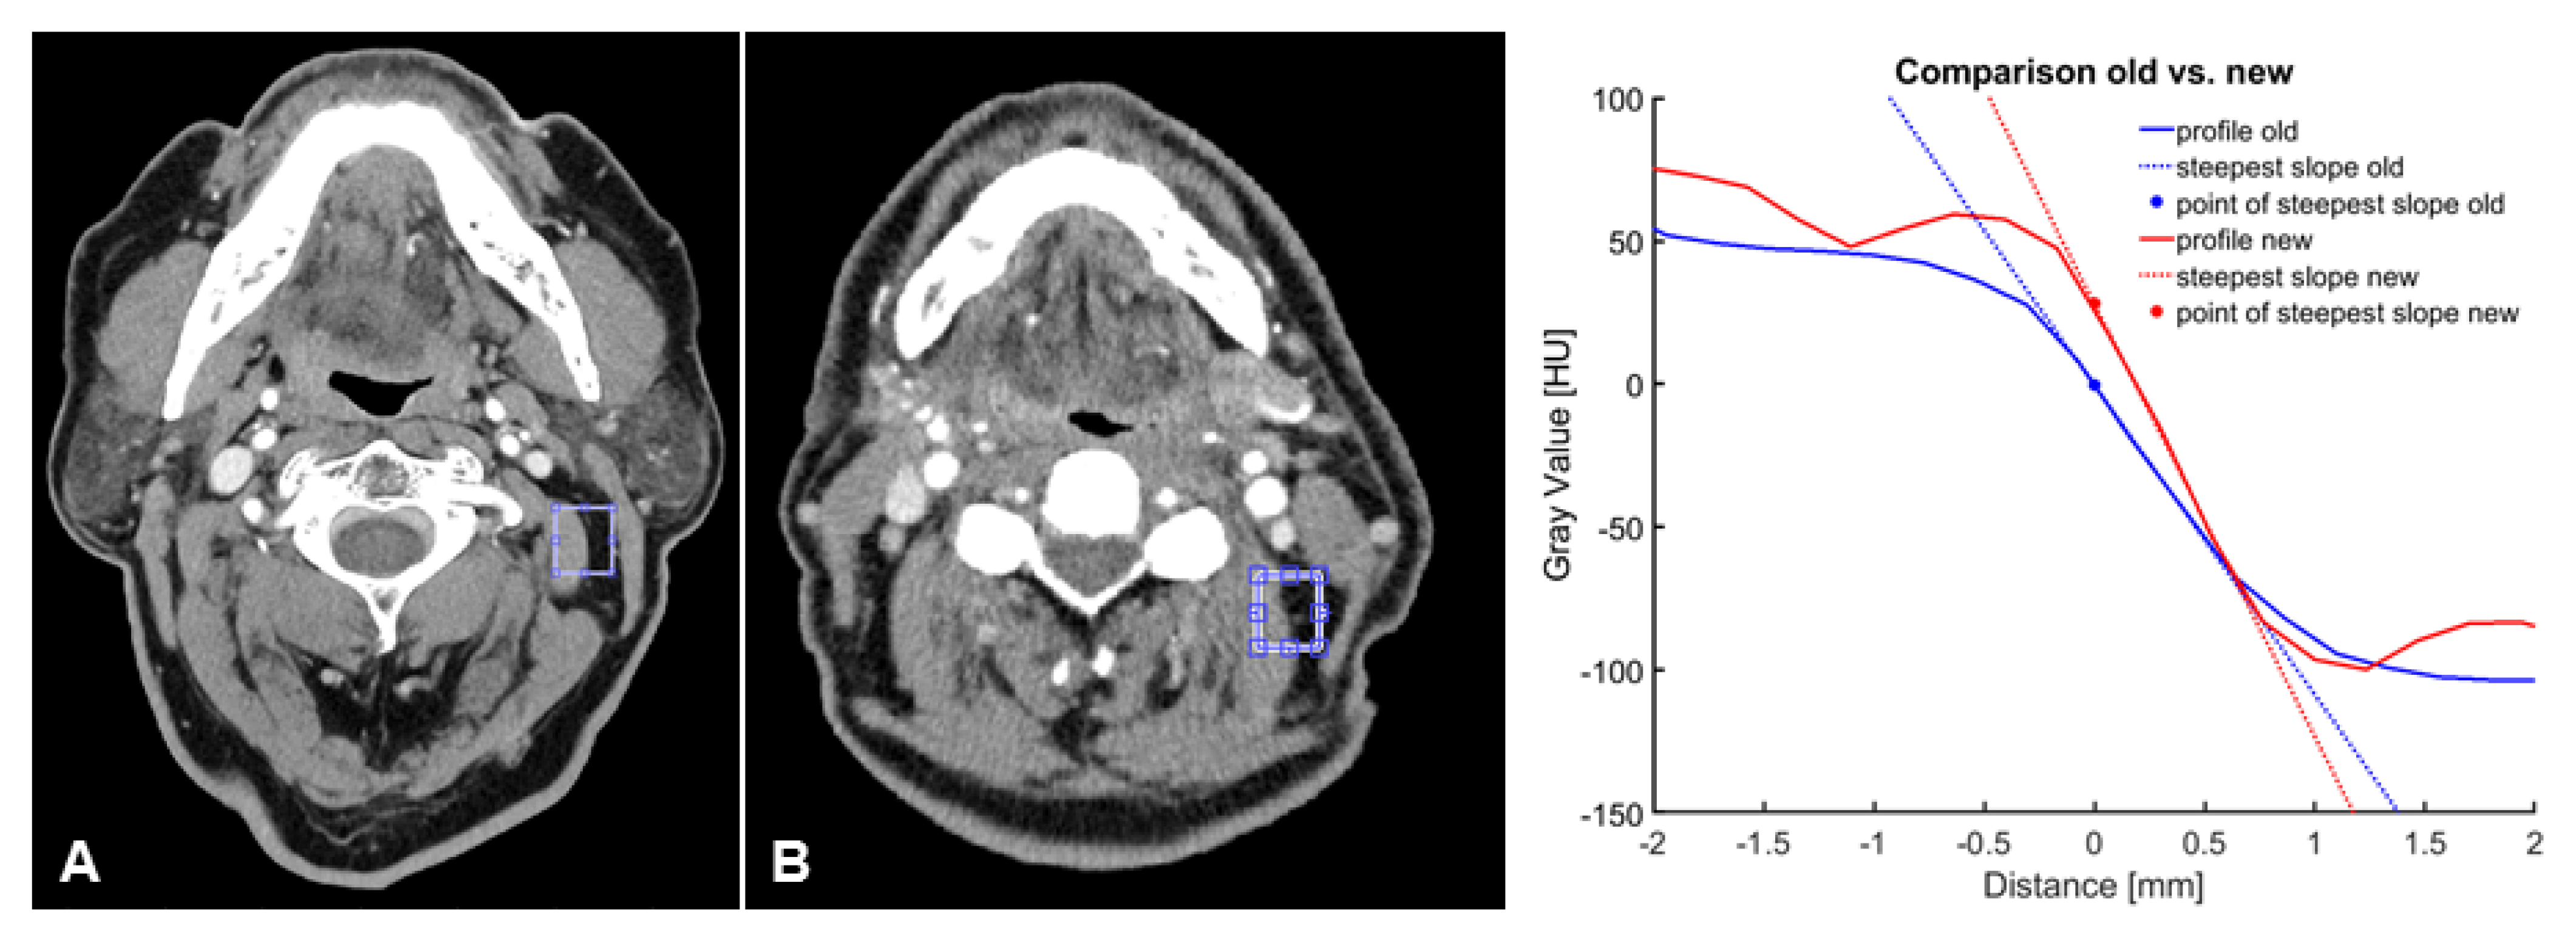

To evaluate objective image parameters, signal-to-noise ratio (SNR, muscle), contrast- to-noise ratio (CNR, muscle, and fat), and the slope of the gray-value transition from fat to muscle tissue as measures of image sharpness were used for an observer-independent description of the image quality. A 3 mm reconstruction was used to determine exemplary slices, selected by a radiologist with 5 years of training, focusing on the cervical soft tissues at the level of the mandible in the proximity of the sternocleidomastoid muscle. On the chosen slice, a small region was selected and the scope of the borderline, which should be analyzed, was defined. Ten profiles perpendicular to the marking were determined over a range of 4.5 mm to each side. As demonstrated in Figure 2, for each of the profiles, the upper and the lower baseline, as well as the steepest slope of the transition over three points, as a measure for edge sharpness, were detected. Furthermore, the median was calculated for all ten profiles.

3.3. Objective Image Quality

The assessment of objective image criteria demonstrated that the UHR-CT images had significantly increased SNR and CNR values, as described in Table 4. As illustrated in Figure 7 and Figure 8, the contrast-to-noise ratio of both CT methods revealed that the steepness of the slope of gray-value transitions between fat and muscle tissue decreased from the NR-CT images: −94.5 ± −5.5 to in UHR-CT images: −168.4 ± −9.4 HU/mm (p < 0.0001).

Figure 7. Comparison of contrast-to-noise-ratio of (A) UHR-CT and (B) NR-CT in a 57-year-old male patient with a squamous cell carcinoma of the left upper jaw.